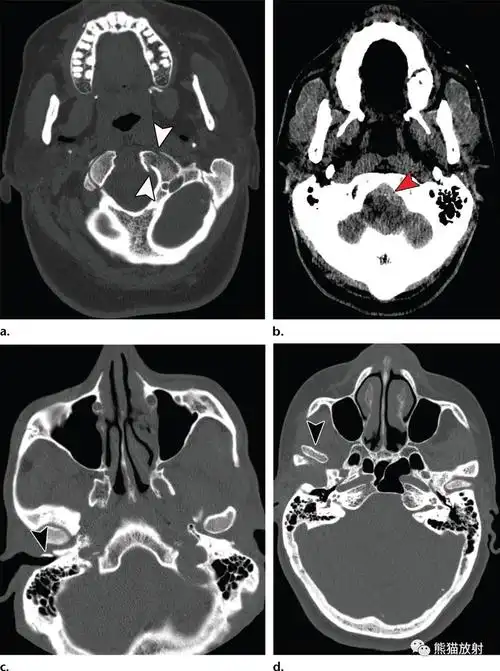

颅底解剖及相关病变丨ct平扫的价值